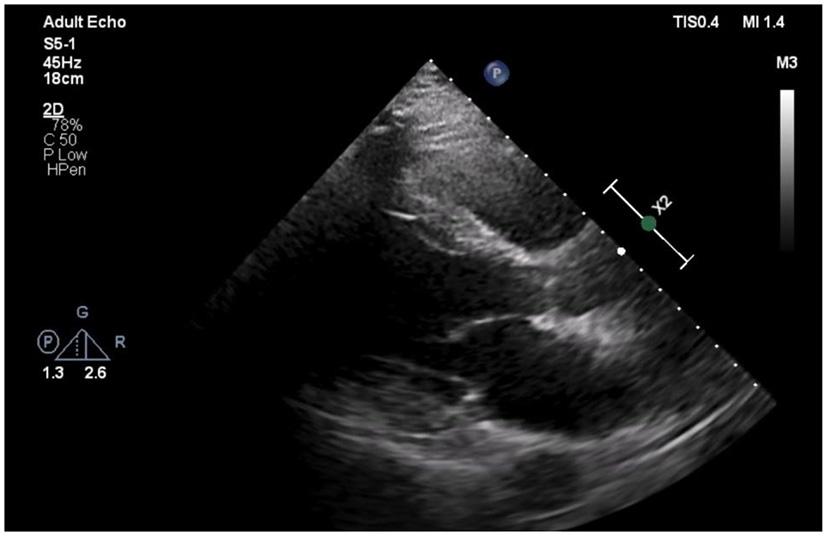

Figure 2

Echocardiogram of Left parasternal axis view shows no pericardial effusion.

The patient was admitted to our coronary care unit as a case of ACS and was started on an ACS management protocol that includes aspirin, clopidogrel, statin, and subcutaneous heparin (enoxaparin 1 mg/kg twice daily). A transthoracic echocardiogram revealed a low normal ejection fraction (EF 50%) with mild anterior wall hypokinesia and no pericardial effusion; otherwise, no abnormality was detected (Figure 2). The patient was stabilized overnight and taken to the coronary catheterization laboratory for a coronary angiogram. The coronary angiogram showed normal left main (LM) artery, and the left anterior descending artery (LAD) exhibited a large pseudoaneurysm in proximal segment with contrast squirted in it and TIMI II-III flow in the distal LAD (Figure 3). The left circumflex artery (LCX) and the right coronary artery (RCA) were observed to be normal. The procedure was stopped, and the patient was urgently referred for a cardiac surgery consultation. Three hours later, he developed acute hypotension with a BP of 75/55 mmHg and HR of 133 bpm. Bolus IV fluid was given, and emergency bedside pericardiocentesis was performed in addition to the removal of 50 cc of fresh blood. The patient's BP stabilized, and he was taken as a lifesaving case to the operating room. Cardiopulmonary bypass (CPB) was established through the cannulation of the femoral vessels. A median sternotomy was performed, and 100 cc of fresh and clotted blood was removed from the pericardial sac. Then, careful examination of the pseudoaneurysm showed spontaneous rupture with contained bleeding. The opening of spontaneous rupture in the LAD was identified as shown in Figure 4, and it was closed with a 3–0 polypropylene continuous suture. Postoperatively, the patient did well. He did not show any signs of either myocardial infarction or left ventricle pump failure. Thus, he was discharged 6 days later in a stable condition.